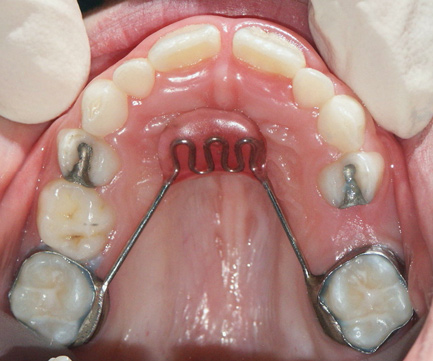

Fig 15. Nance arch (maxilla).

Figure 15

In cases of premature loss of primary teeth or missing permanent teeth, space maintenance is crucial.42 Possible causes of such tooth loss include caries, trauma, or a congenital disorder. If proper spacing is not maintained, mesial tooth drift may occur,43,44 which can lead to impaction or ectopic eruption of permanent teeth, as previously discussed. Various designs of space maintainers are available, depending on the location in the mouth that needs space preservation. Common devices include the Nance arch for the maxilla (Figure 15), a lower lingual holding arch for the mandible (Figure 16), and a band and loop or distal shoe for unilateral cases of space loss (Figure 17). Band and loop appliances seem to have the highest longevity intraorally; generally, unilateral devices fare better than their bilateral counterparts.45